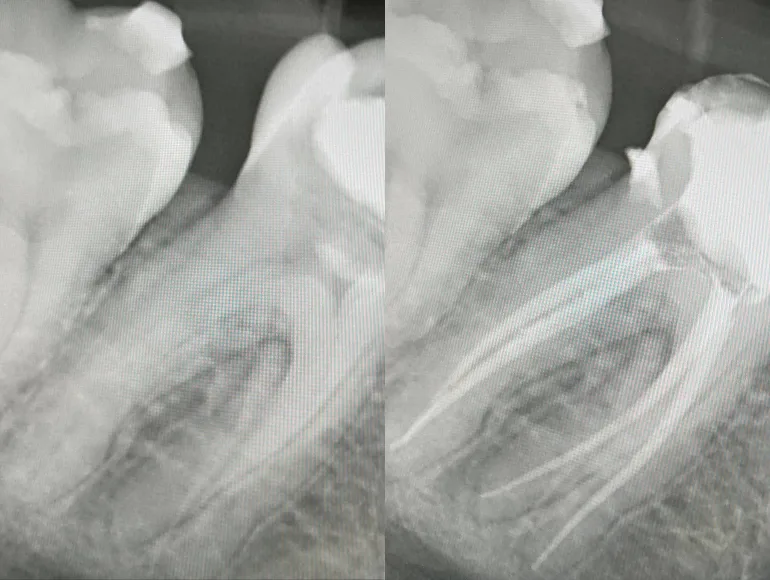

Teeth With Unconventional Number of Roots or Canals

Case by Dr. Taha Azimaie: Identifying unconventional number of roots and canals is the key in long term survival of the tooth. Tooth number 4, upper right premolar, usually have 1 pulp chamber, 1 root and 1 canal. This tooth have complex shape with 2 pulp chambers and 3 canal.